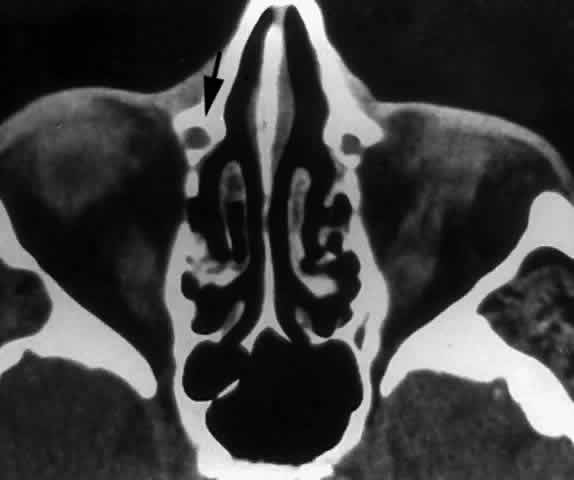

Fig. 29. In this computerized tomographic scan of the orbit, the medial wall of the nasolacrimal canal is almost entirely formed by the maxilla (arrow).